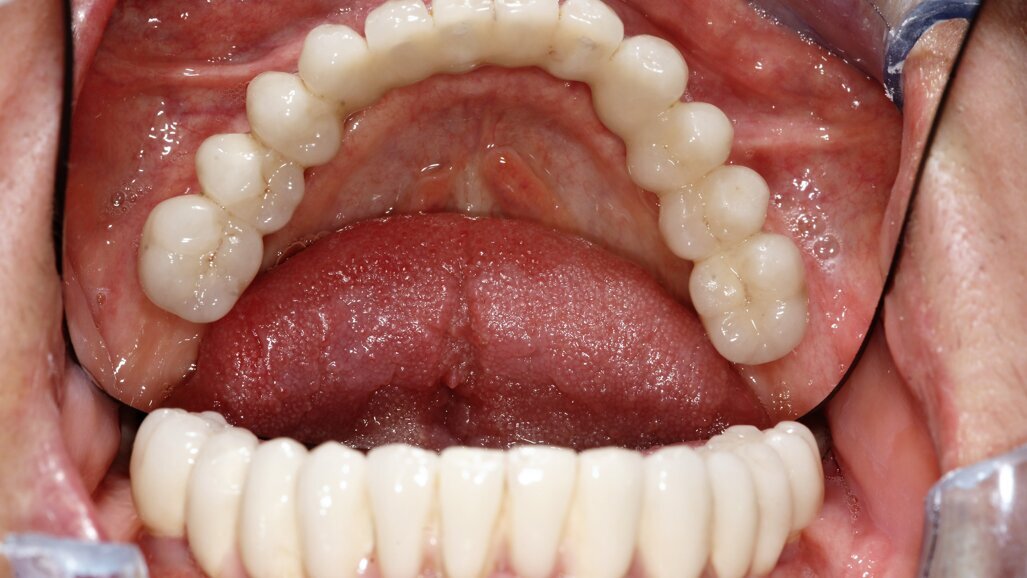

przygotowanej wcześniej protezie czasowej metodą bezpośrednią. Czasowe uzupełnienie protetyczne osadzono, używając cementu tymczasowego (Ryc. 5 i 6). Zlecono wykonanie zdjęcia techniką CBCT (Ryc. 7). Wizytę kontrolną wyznaczono następnego dnia, a szwy zostały usunięte po 10 dniach.

Po upływie 3 miesięcy czasowe uzupełnienie protetyczne (Ryc. 8) zostało wymienione na cementowaną pracę ostateczną (Ryc. 9),

W kwietniu 2017 r. został wykonany status periodontologiczny pozostałego uzębienia i wszczepionych implantów (Ryc. 12) i ponowne badanie CBCT (Ryc. 13- 15). Stan 3 lata po zabiegu przedstawiono na rycinach 16-18. Pacjentka jest ujęta w programie Recall w cyklu 6-miesięcznym od dnia wykonania zabiegu.